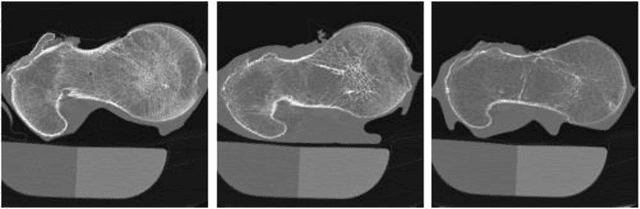

Abstract:The ability of Minkowski Functionals to characterize local structure in different biological tissue types has been demonstrated in a variety of medical image processing tasks. We introduce anisotropic Minkowski Functionals (AMFs) as a novel variant that captures the inherent anisotropy of the underlying gray-level structures. To quantify the anisotropy characterized by our approach, we further introduce a method to compute a quantitative measure motivated by a technique utilized in MR diffusion tensor imaging, namely fractional anisotropy. We showcase the applicability of our method in the research context of characterizing the local structure properties of trabecular bone micro-architecture in the proximal femur as visualized on multi-detector CT. To this end, AMFs were computed locally for each pixel of ROIs extracted from the head, neck and trochanter regions. Fractional anisotropy was then used to quantify the local anisotropy of the trabecular structures found in these ROIs and to compare its distribution in different anatomical regions. Our results suggest a significantly greater concentration of anisotropic trabecular structures in the head and neck regions when compared to the trochanter region (p < 10-4). We also evaluated the ability of such AMFs to predict bone strength in the femoral head of proximal femur specimens obtained from 50 donors. Our results suggest that such AMFs, when used in conjunction with multi-regression models, can outperform more conventional features such as BMD in predicting failure load. We conclude that such anisotropic Minkowski Functionals can capture valuable information regarding directional attributes of local structure, which may be useful in a wide scope of biomedical imaging applications.